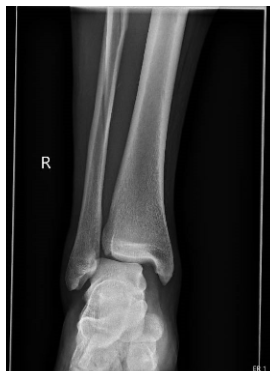

Image A, B, C: Right Ankle XR (Obl, Lat, AP)

Impression: Acute, comminuted, mildly displaced fracture of the mid fibular diaphysis. Marked widening of the medial ankle joint space compatible with syndesmotic ligamentous injury. Talar dome appears intact.